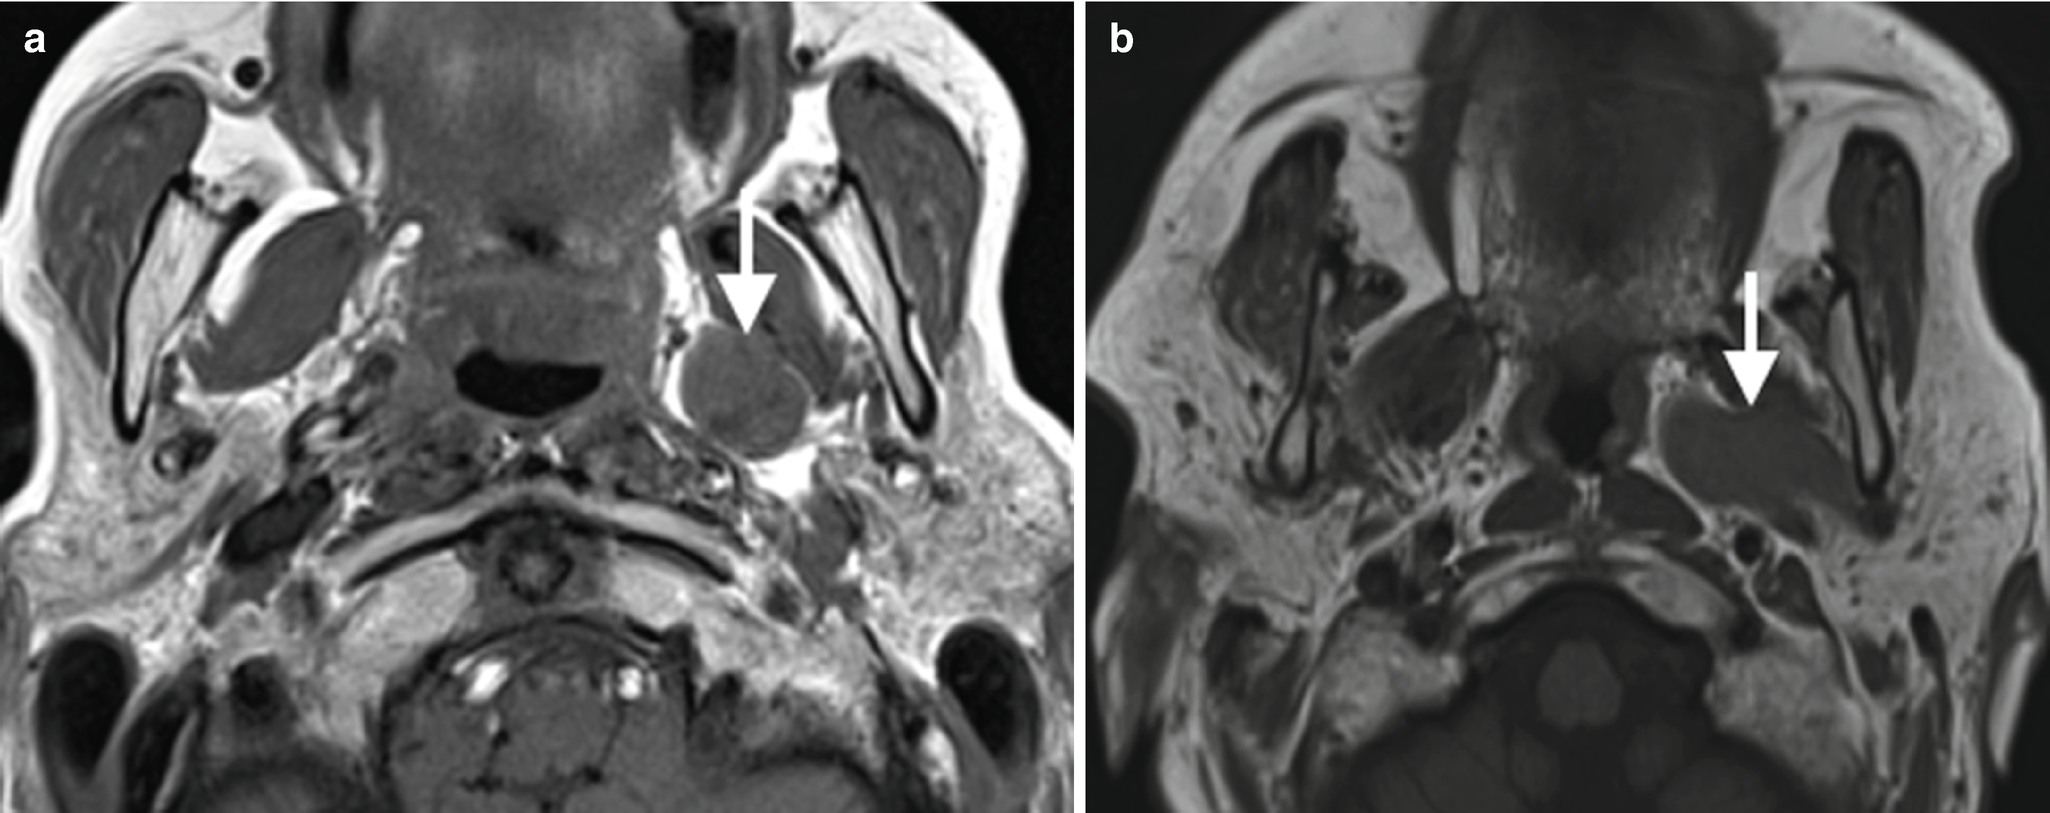

Approach To Masses In Head And Neck Spaces Springerlink